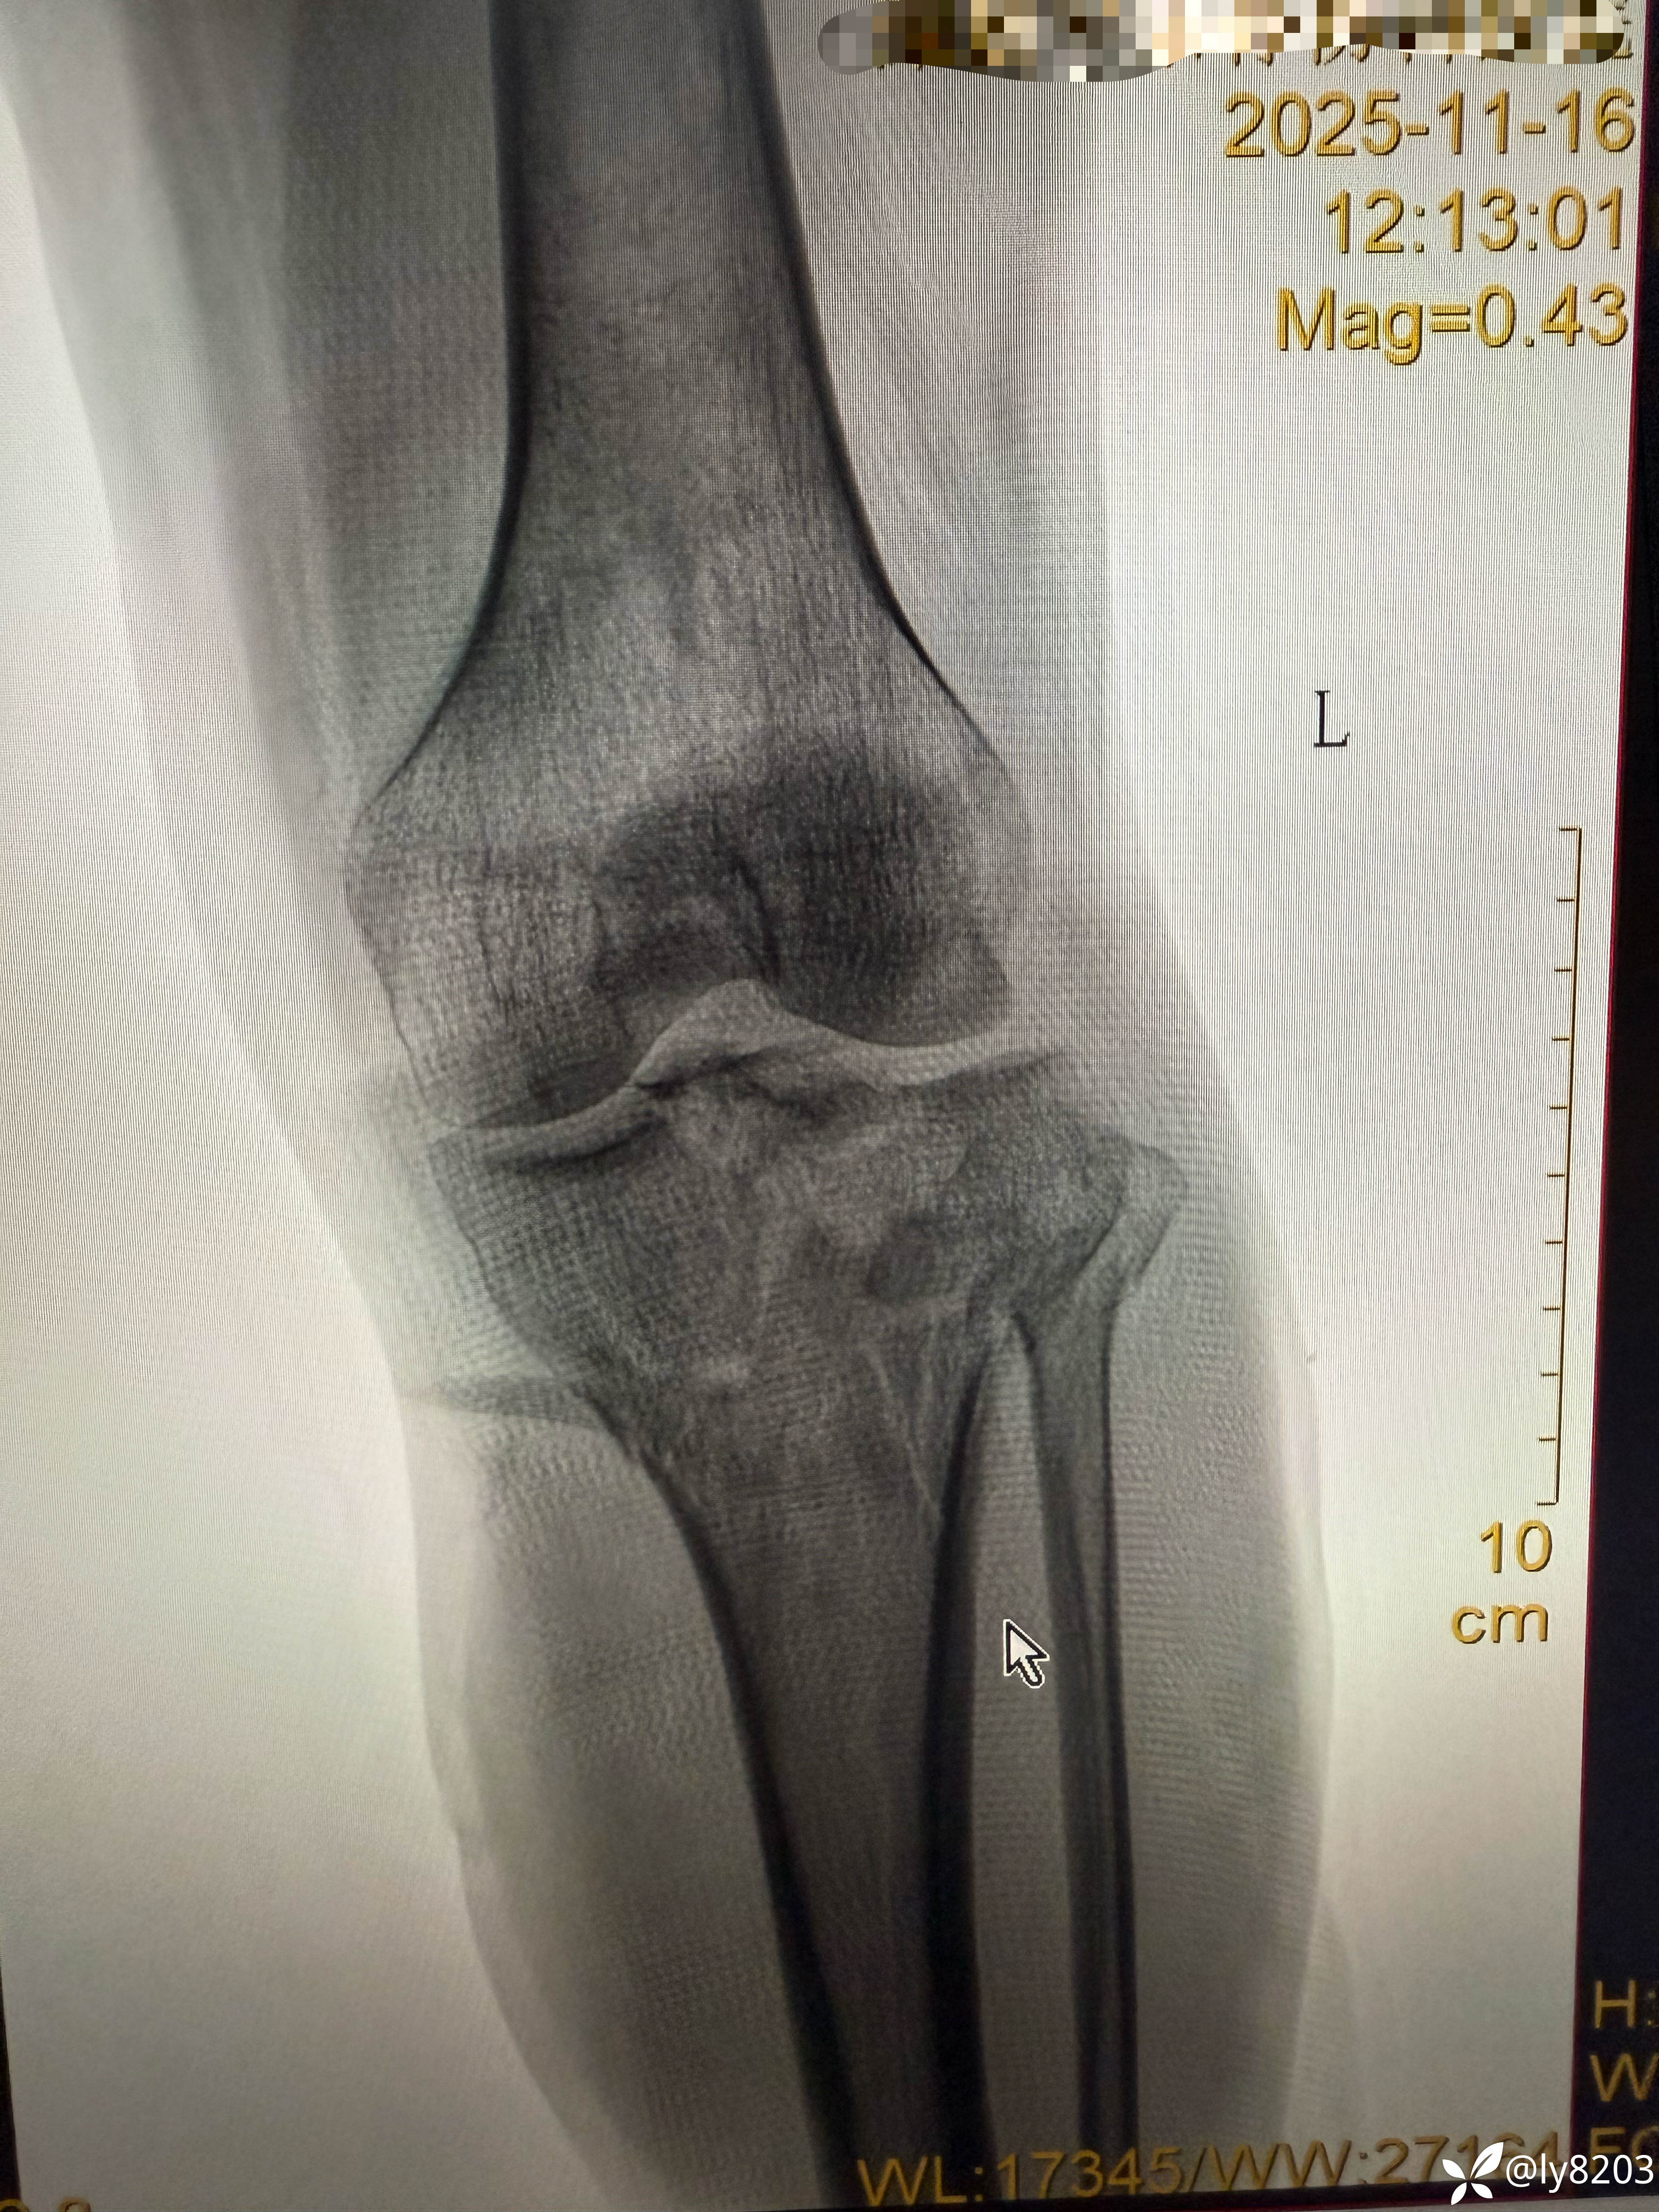

中年男子,外院转入患者,先看图